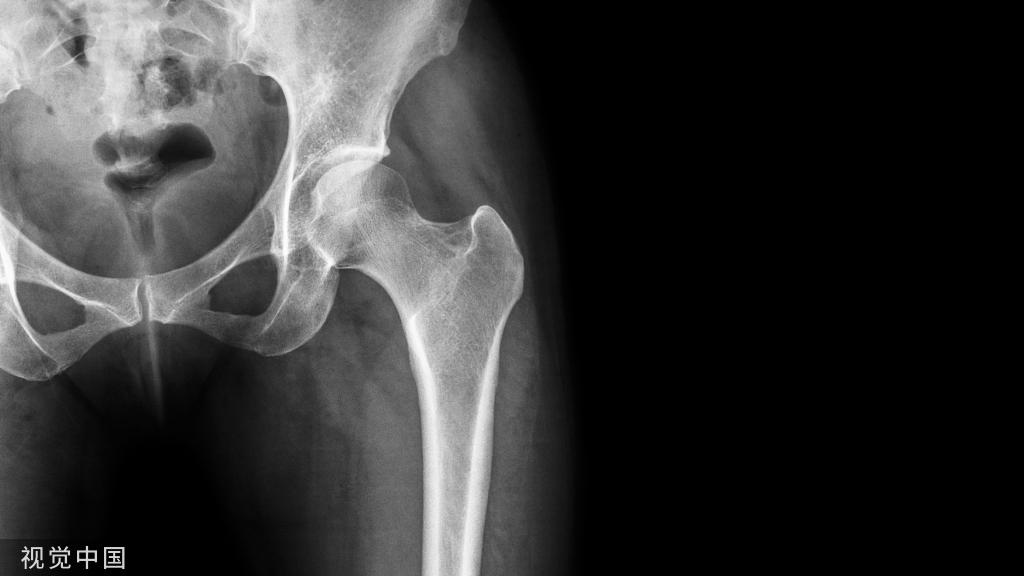

断端断裂通常是疲劳断裂,也有部分外伤导致的断裂。疲劳断裂通常在好几个月到几年的时间不等。骨折长期不愈合所导致

骨折复位不良、断端无接触、没有动力化、粗隆下骨折应力较大。骨折延迟愈合,6个月的时候发生了断钉

7个月 骨折延迟愈合断钉